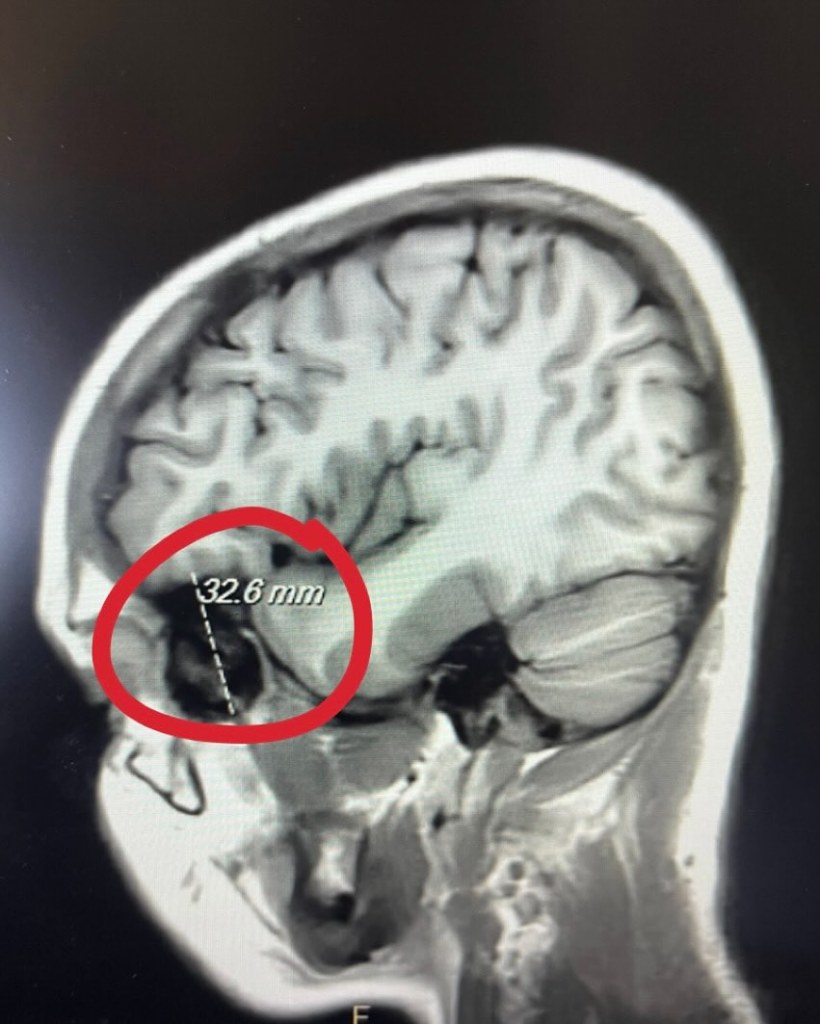

A week or so later I couldn’t take it anymore, so I went back and told them I needed an MRI. I finally got the MRI and they called us almost immediately after. I was half asleep on the couch when I heard the doctor say on the phone “they found a mass” to my mom. My face went pale, my body was hot, and I ran outside to throw up.

My immediate thoughts were not ones you want to be thinking when you’re 20 years old and still have so much life left you want to experience. My family came to see me that day, but I was so out of it I could barely interact. We had no idea how big the tumor was or if it was cancerous or not.

The next day I went in to get a cat scan with contrast. It was confirmed that the tumor was about the size of a golf ball, smashed in my orbital region—running from behind my eye to the front of my ear. It was millimeters away from my brain. The doctor confirmed that it did not look cancerous, but if we would have waited much longer it would have grown into my brain. A tumor that size hitting my brain could have been extremely destructive. I know that God’s timing was perfect, and He saved me from a potential disaster.